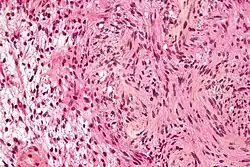

Micrograph of a schwannoma, a tumor seen in neurofibromatosis type II. HPS stain.

The so-called acoustic neuroma of NF2 is in fact a schwannoma of the nervus vestibularis, or vestibular schwannoma. The misnomer of acoustic neuroma is still often used. The vestibular schwannomas grow slowly at the inner entrance of the internal auditory meatus (meatus acousticus internus). They derive from the nerve sheaths of the upper part of the nervus vestibularis in the region between the central and peripheral myelin (Obersteiner-Redlich-Zone) within the area of the porus acousticus, 1 cm from the brainstem.